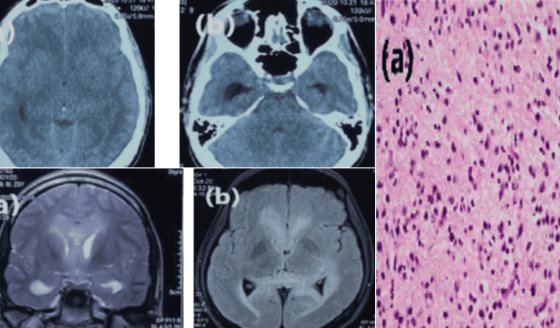

El mieloma múltiple es una enfermedad hematológica maligna que se caracteriza por la proliferación anormal de células plasmáticas en la médula ósea.